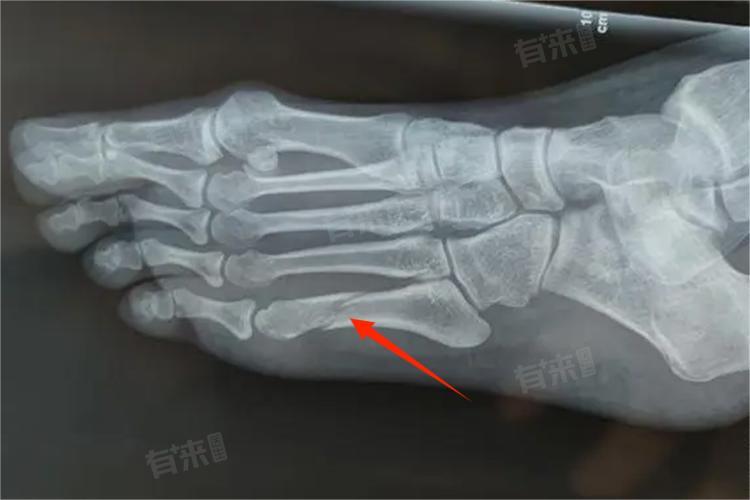

第五跖骨骨折是一种常见的足部损伤,通常由外物撞击、高空坠落或重物砸伤等暴力损伤导致。关于这种骨折是否属于轻微骨折,需要根据骨折的具体情况来判断。

- 第五跖骨骨折包括多种类型,如第五跖骨基底部骨折、跖骨干骨折和跖骨颈骨折等,不同类型的骨折在损伤程度和治疗方法上存在差异。第五跖骨基底部骨折,通常由于足极度内翻和腓骨短肌的牵拉引起,多数无移位,但有时会有裂开。这种类型的骨折在多数情况下属于轻微骨折,可以通过保守治疗,如石膏或氧化锌绷带固定,来促进骨折愈合。

- 如果第五跖骨骨折受伤比较严重,如发生粉碎性骨折、骨折端移位显著或伴有神经、血管、肌腱损伤,则属于重度跖骨骨折。这种情况下,骨折部位可能发生开放,伴有大量出血和剧烈疼痛,属于比较严重的骨折,需要尽快由创伤骨科医生进行治疗。治疗可能包括手术内固定、清创手术等,以确保骨折顺利恢复。